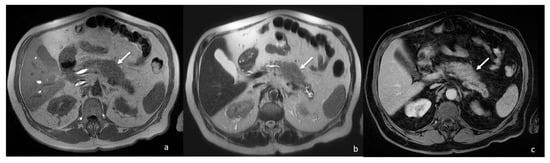

Stocky/Packed Pancreas: A Case of Focal Drug-Induced Acute Pancreatitis Mimicking Cancer

Di Serafino, M.; Ronza, R.; D’Auria, D.; Fiorentino, R.; Arundine, D.; De Leone, A.; Picascia, S.; Martino, A.; Crolla, E.; Campione, S.; et al. Stocky/Packed Pancreas: A Case of Focal Drug-Induced Acute Pancreatitis Mimicking Cancer. Tomography 2022, 8, 2073-2082. https://doi.org/10.3390/tomography8040174